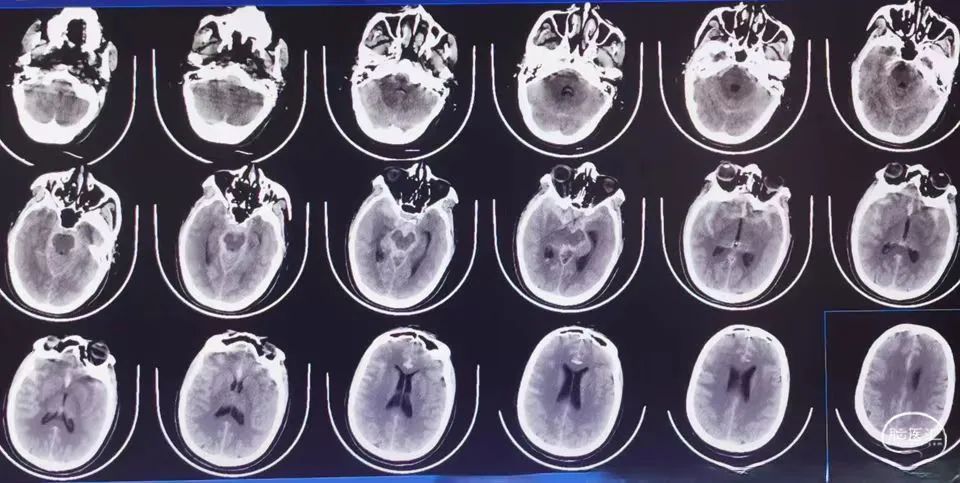

现病史:患者于6小时前无明显诱因突发剧烈头痛,伴随左侧肢体偏瘫,就诊于我院急诊,查头颅CT显示:蛛网膜下腔出血;头颈部CTA显示:右侧颈内动脉眼段动脉瘤。以“蛛网膜下腔出血”收入我科。

体格检查:神志嗜睡,呼之可应,问答合理,Hunt-Hess II级,fisher分级3级,双瞳等大正圆,对光反射迟钝,颈软无强直,左侧肢体肌力0级,右侧有自主活动。

术前头颅CT及DSA检查显示:患者右侧颈内动脉眼段有一宽颈动脉瘤。

自发性蛛网膜下腔出血:右侧颈内动脉眼段血泡样动脉瘤破裂出血。